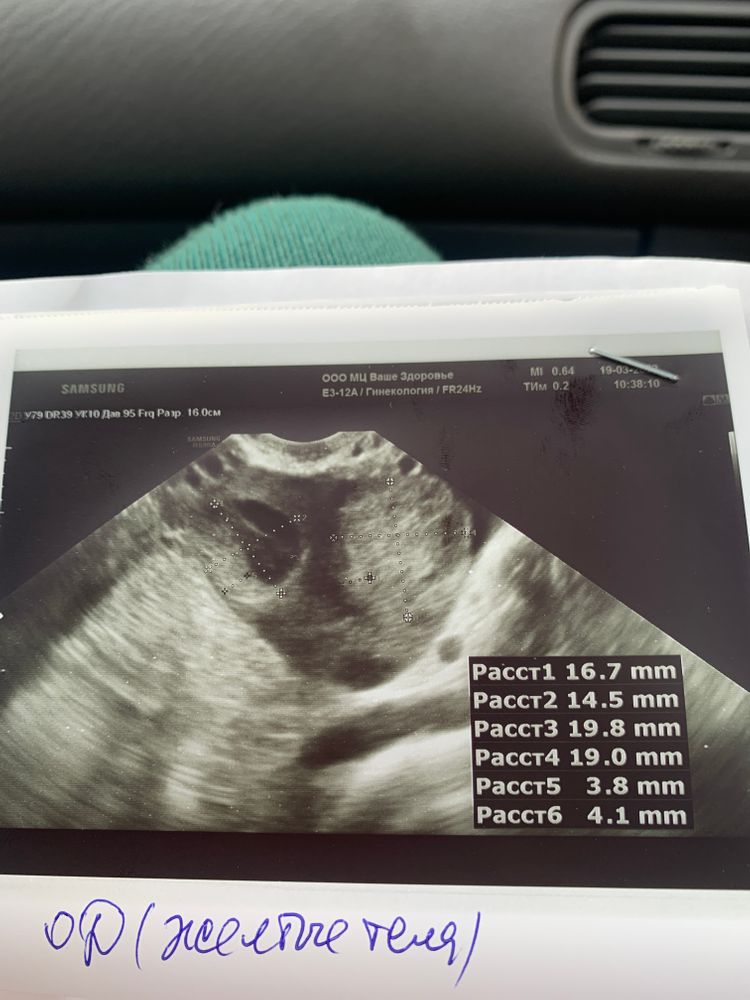

Итоги 1 стимуляции.

Отличный результат, хороший эндик, больше и не надо после О. Ну теперь ждём фото с //!